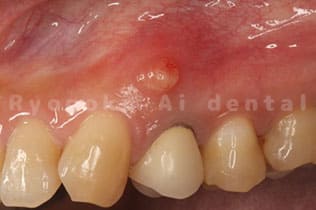

Case03

-

術前

- 原因

- 歯根破折

- 治療内容

- インプラント治療

- 治療費用

- 1,200,000円

左下の歯が腫れているとのことでご来院された患者様です。歯が割れていたため、抜歯となり、2本分歯がなくなったため、インプラントを2本入れました。手術時の痛みもなく、大きなトラブルもなく、非常に満足されています。

<リスク・副作用>

治療後、痛みや違和感、出血、腫れなどが出る事があります。喫煙者、糖尿病などの方の場合、歯が生着しない場合があります。